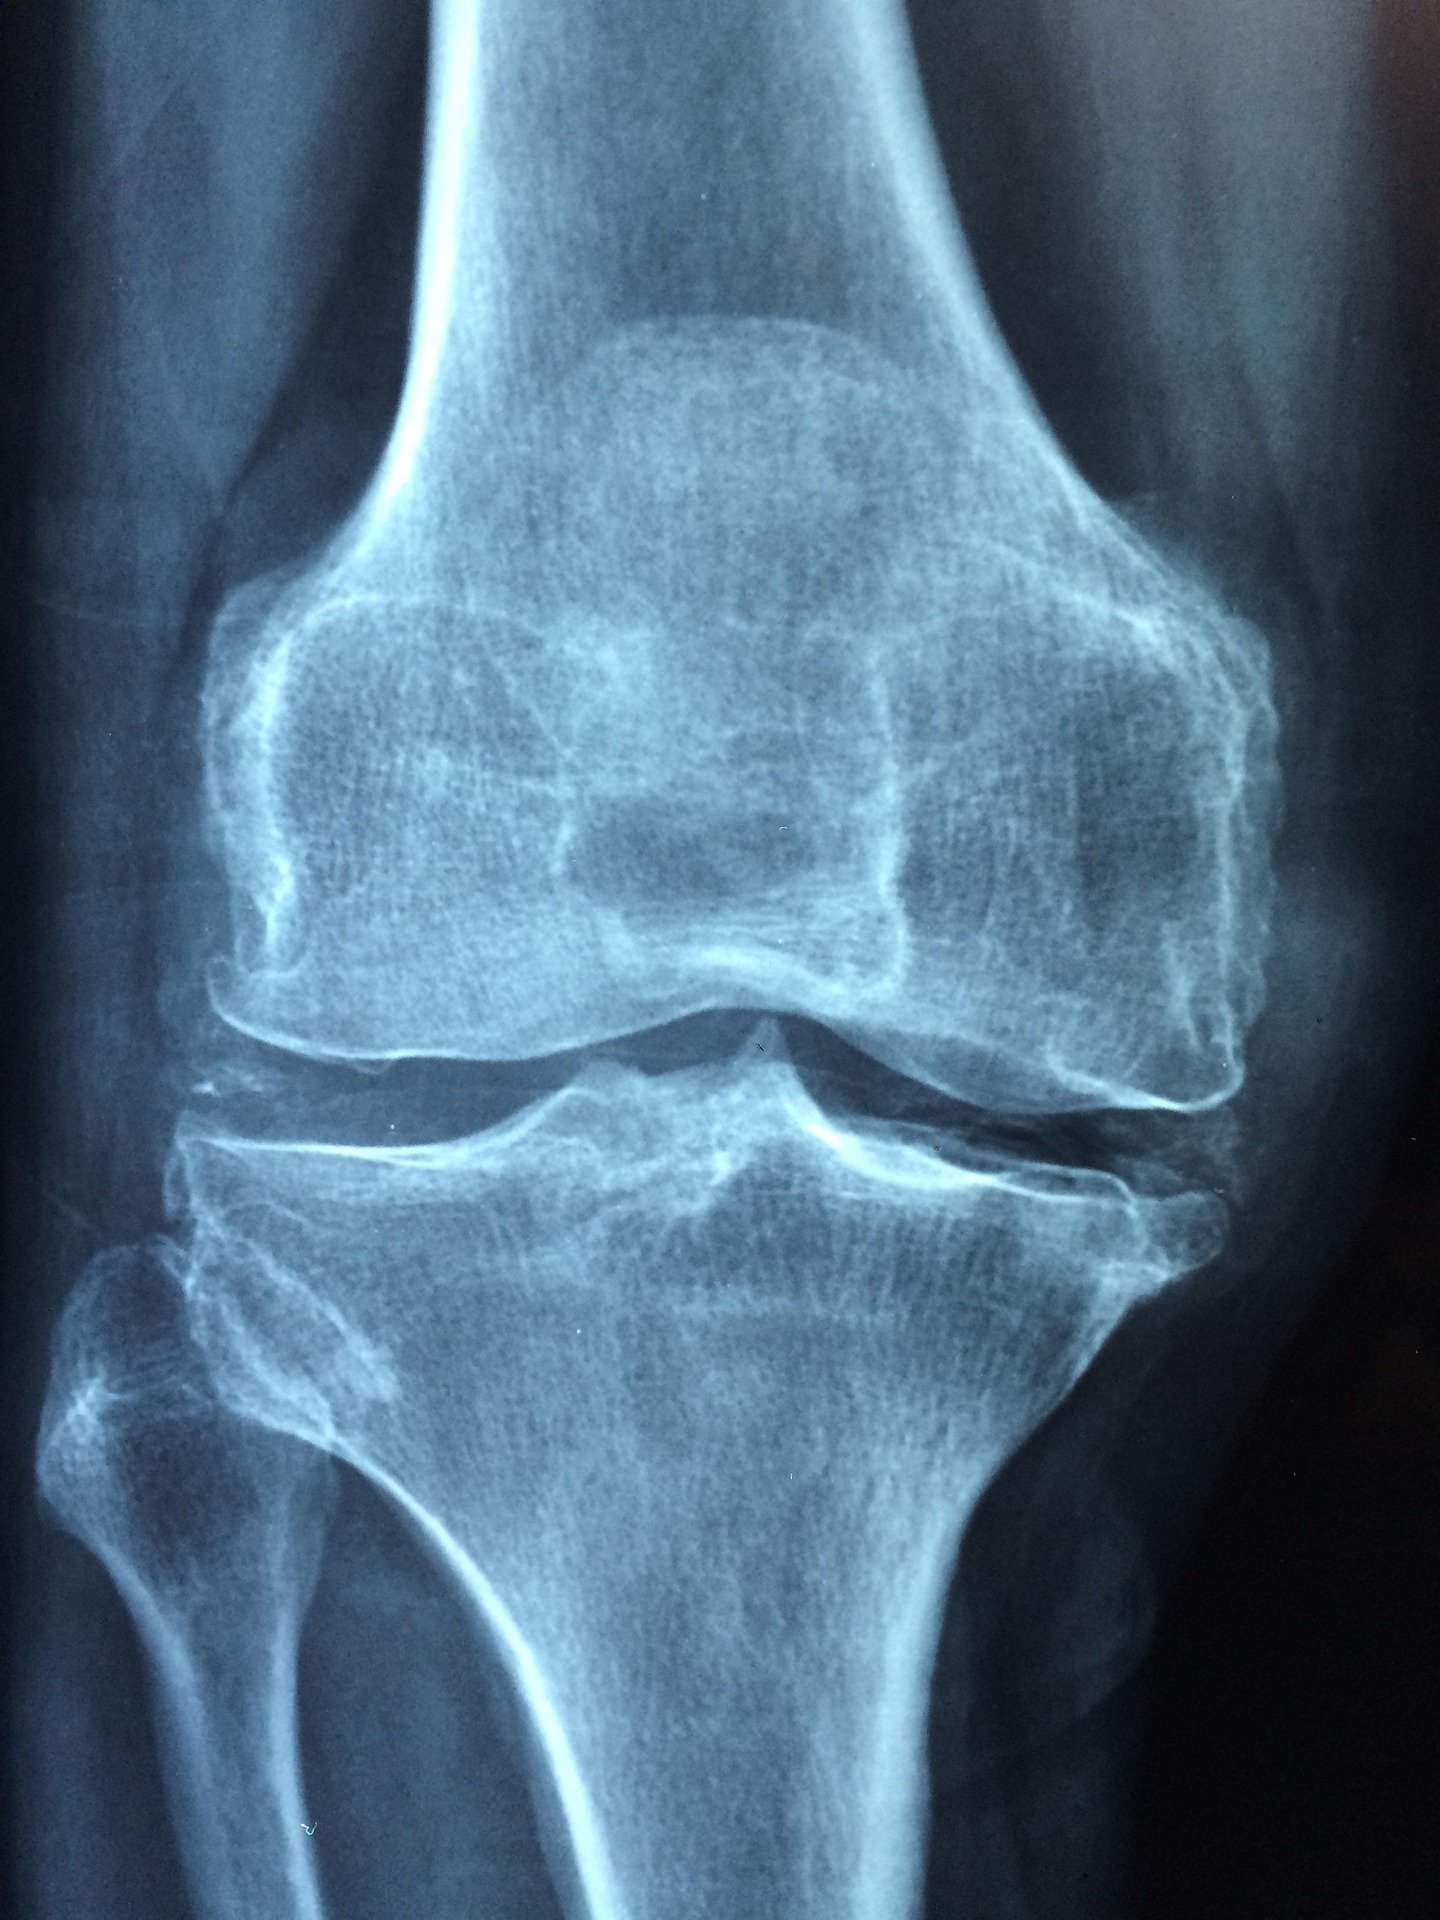

관절 통증은 어느 날 갑자기 찾아오는 것처럼 느껴지지만 사실은 오래 쌓인 신호의 결과였습니다.

가장 흔한 실수는 통증을 나이 탓으로 넘기는 것입니다. “이 정도는 다 아프지” “며칠 지나면 괜찮아지겠지”

관절은 참는다고 좋아지지 않는다는 사실을 뒤늦게 알게 되었습니다.

관절이 아프면 움직이지 않는 것이 답처럼 느껴집니다.

하지만 움직임을 완전히 줄이자 오히려 관절 주변 근육이 약해지고 통증이 더 자주 나타났습니다.